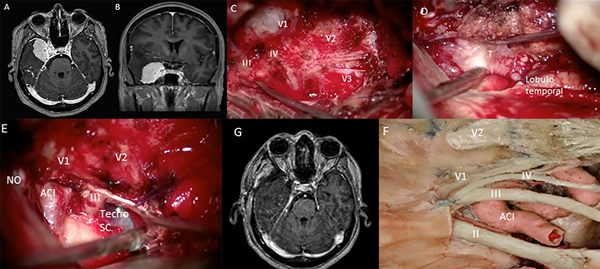

Mujer de 43 años con antecedente de trastorno depresivo que intercurre con crisis comiciales. El examen neurológico fue normal. La resonancia magnética de cerebro mostró lesión extra axial de la pared lateral del seno cavernoso izquierdo sin afectación de la ACI cavernosa (Fig. 4 A,B). El paciente fue sometido a un abordaje pretemporal izquierdo con peeling de la fosa media (Fig. 4 C,D) y se logró la resección total del tumor (Fig. 4 E,F). Evolucionó satisfactoriamente en el postoperatorio y la RMN mostró una resección total macroscópica del tumor (Fig. 4 G). Un año después de la cirugía el paciente sigue neurológicamente sin déficit con excelente calidad de vida.

FIG 4. Caso 2. A y B. RM preoperatoria que muestra un tumor cavernoso de la pared lateral derecha. C. El desprendimiento de la fosa media expuso las ramas del trigémino. D. Imagen intraoperatoria que muestra la disección del tumor del lóbulo temporal. E. Usar el techo del seno cavernoso para extirpar el tumor. F. Pieza de cadáver que muestra la relación de las estructuras neurovasculares del techo y la pared lateral del seno cavernoso. G. Resonancia magnética posoperatoria que muestra una resección total macroscópica del tumor. ON, Nervio Óptico, Nervio Oculomotor III, Nervio troclear IV, Arteria Carótida Interna ACI, Tumor T, Seno Cavernoso SC.